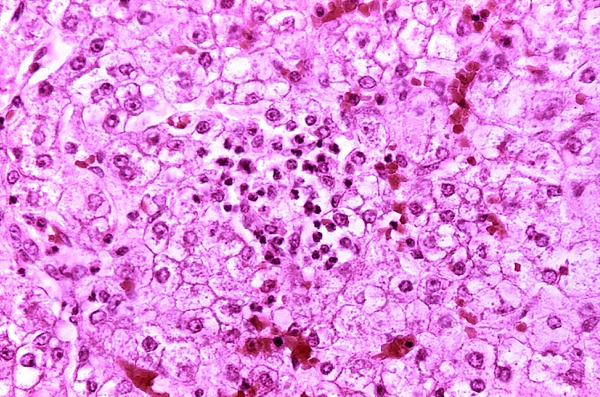

В основе синдрома лежит генерализованное повреждение митохондрий вследствие ингибирования окислительного фосфорилирования и нарушения β-окисления жирных кислот.